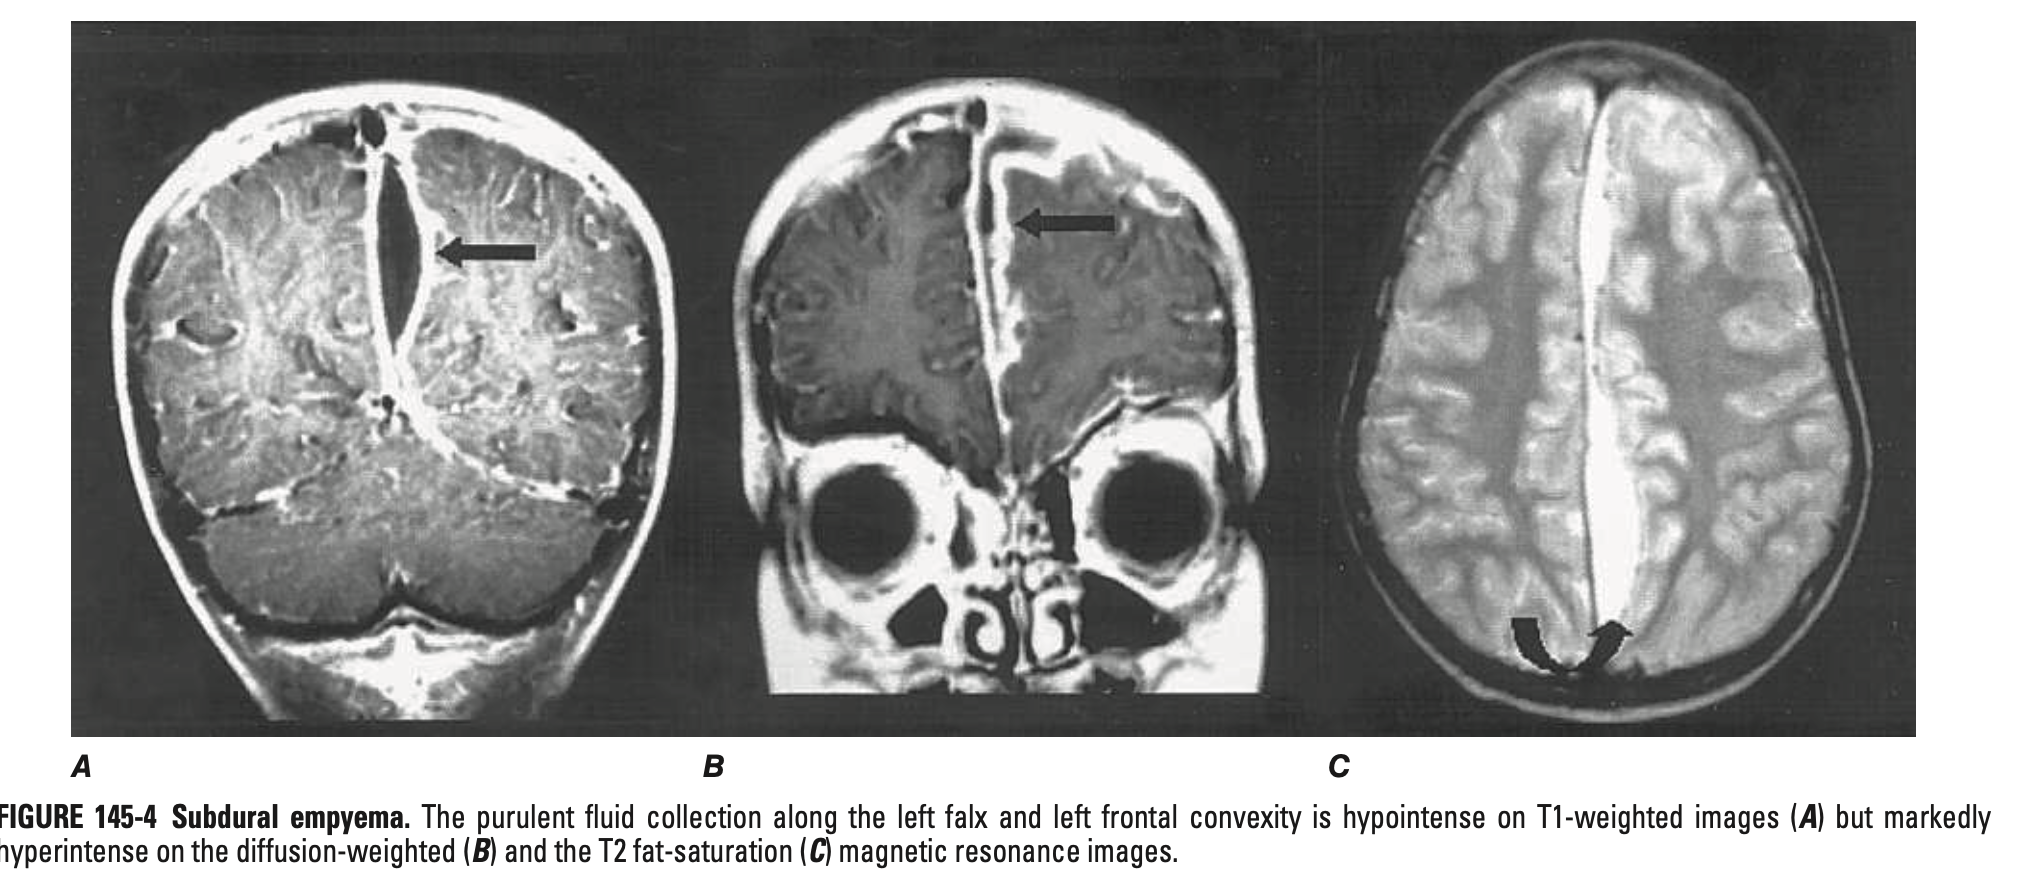

경막하 농흉 (Subdural empyema) / 경막 외 농양 (Epidural abscess)

• 정의: 경막하/경막외 공간에 농양이 형성

• 임상 양상

• 발열, 점점 악화되는 두통

• 알려진 부비동염이 있으면서 두통 및 발생하는 경우 반드시 의심

• 경부 강직, 경련, 국소 신경학적 증상/징후, 뇌압상승의 징후

• 병변 반대측 hemiparesis 흔하게 발생

• 진단: MRI > CT